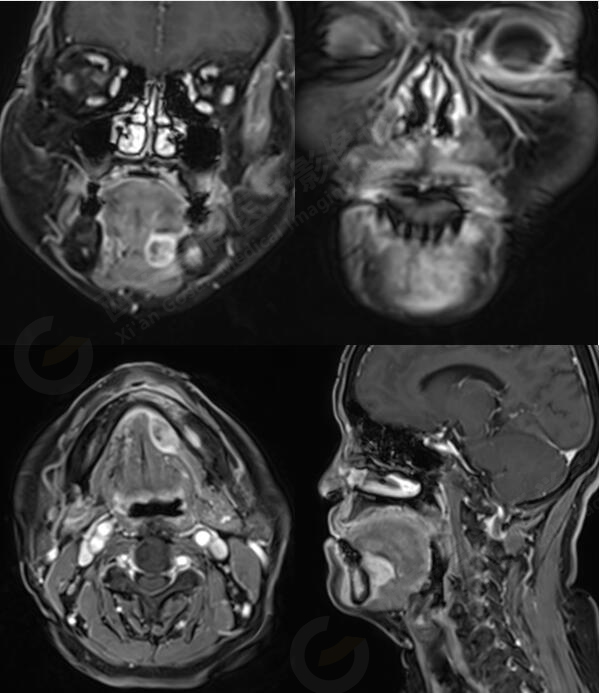

MR影像圖

MR平掃+增強:左側口底部下頜骨周圍見大小約3.4cmX3.3cmX3.3cm的團塊狀稍長T1稍長T2信號,壓脂像上呈稍高信號,病灶邊緣清晰,形態(tài)不規(guī)則,下頜骨骨質破壞,強化掃描示:左側下頜骨周圍病灶呈不均勻明顯強化,邊緣強化為著。

左側口底部下頜骨周圍占位,鱗Ca可能。

此腫瘤位于左側口底部下頜骨周圍,未見明顯囊變,下頜骨骨質破壞,DWI像上病灶呈明顯低信號,ADC圖上呈低信號,增強后不均勻明顯強化,病人年齡較大,可以考慮惡性腫瘤,口底好發(fā)鱗癌。

4.影像學表現(xiàn):MRI具有較高的軟組織分辨率,可多平面成像,能清晰顯示腫瘤的大小形態(tài)及信號特征,并準確地評估病灶范圍及周圍結構受累情況。形態(tài)多不規(guī)則,邊界不清,T1WI呈等信號,T2WI呈不均勻的高或稍高信號,增強后可見明顯強化。在T2WI上可出現(xiàn)低信號分隔,增強后分隔強化,呈多發(fā)小囊狀改變,此征象對于ACC的診斷具有一定的特異性。